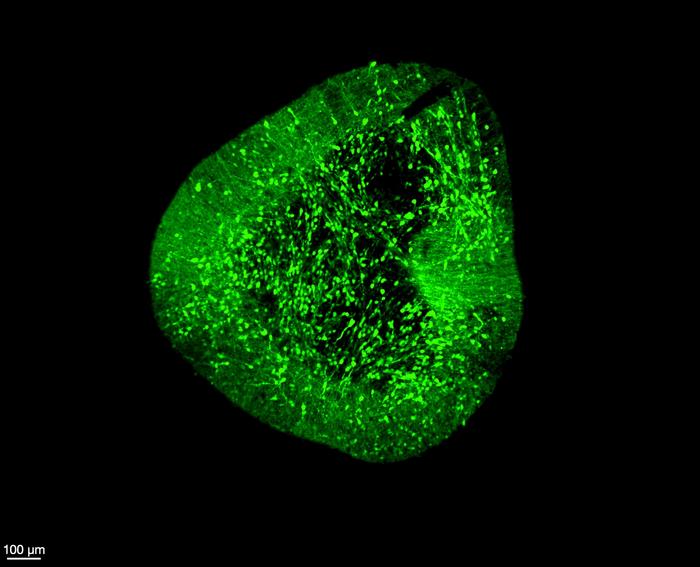

Midbrain dopaminergic neurons under a microscope

Credit: Hilary Toh, Duke-NUS Medical School